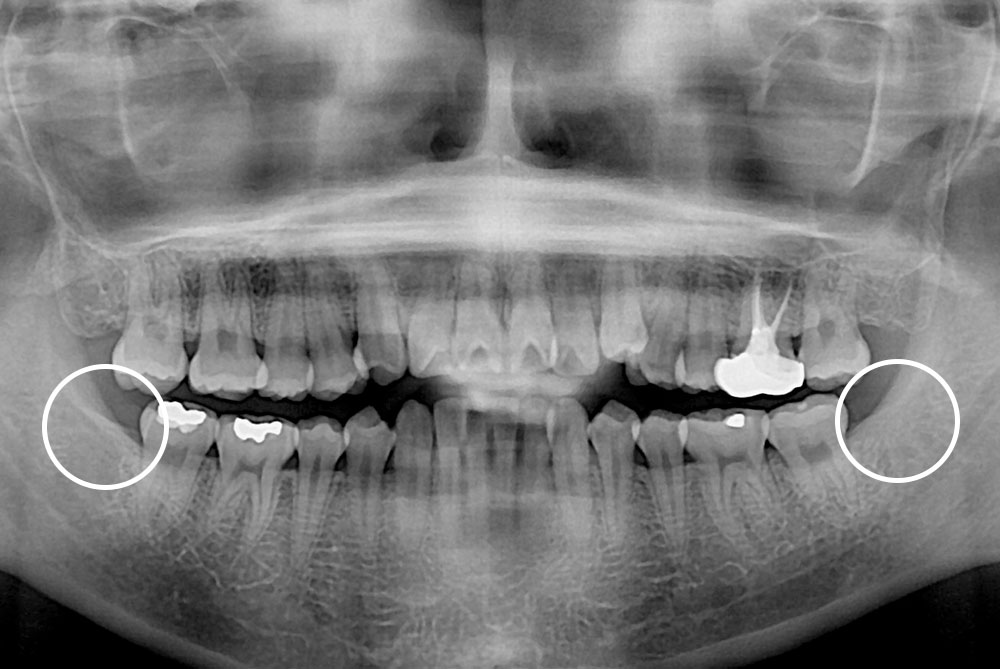

[사랑니] 매복 사랑니 발치

치료후 : 2019-10-18

세종치과는 구강악안면외과학 박사이신 원장님이 발치하는 치과입니다.